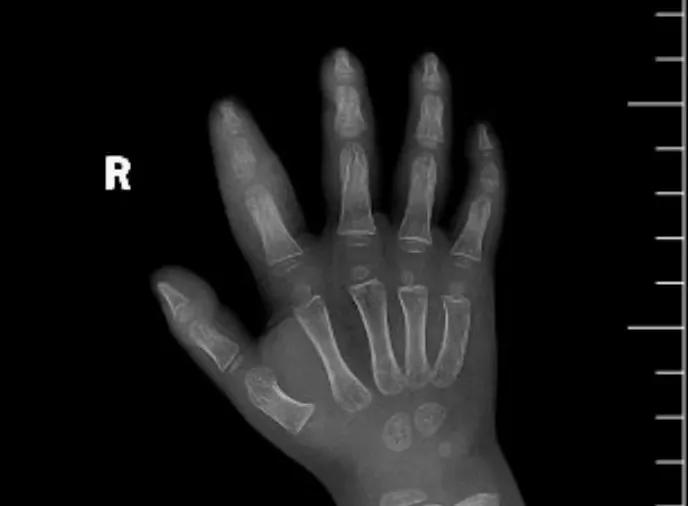

近日,市二院顯微外科接診一名3歲半的小患者,被玉米葉割傷右食指,因家長疏忽大意,導(dǎo)致一個(gè)小小的傷口竟然發(fā)展成了骨髓炎。來院時(shí)患兒右食指腫脹明顯,既不能伸也不能彎,皮膚發(fā)燙,疼得哇哇大哭。

第三天開始,月月哭鬧不止,一直說手疼,怎么哄也不行,于是在當(dāng)?shù)蒯t(yī)院治療了10來天,然而月月的手指依然腫得像個(gè)胡蘿卜,疼痛感依然存在。此時(shí),月月的媽媽才覺得事情不大對勁,于是經(jīng)過打聽,慕名來到市二院顯微外科。入院后,經(jīng)檢查發(fā)現(xiàn),月月的右食指骨質(zhì)有侵蝕,骨骺有缺損,甚至?xí)绊懸院笫种傅陌l(fā)育。聽到這個(gè)消息,月月媽媽感覺心都揪住了。

隨后,經(jīng)顯微外科團(tuán)隊(duì)充分的討論,制定了科學(xué)細(xì)致的治療方案,為月月做了感染灶清除及手指的開放引流,并留取了標(biāo)本做細(xì)菌培養(yǎng),為進(jìn)一步的合理用藥提供依據(jù)。經(jīng)過兩周的治療,月月的手指終于順利消腫愈合,并且手指功能活動良好。說起這一個(gè)多月的煎熬,月月媽媽不禁落淚,但總算是治愈了,笑容又重新回到她們一家的臉上。